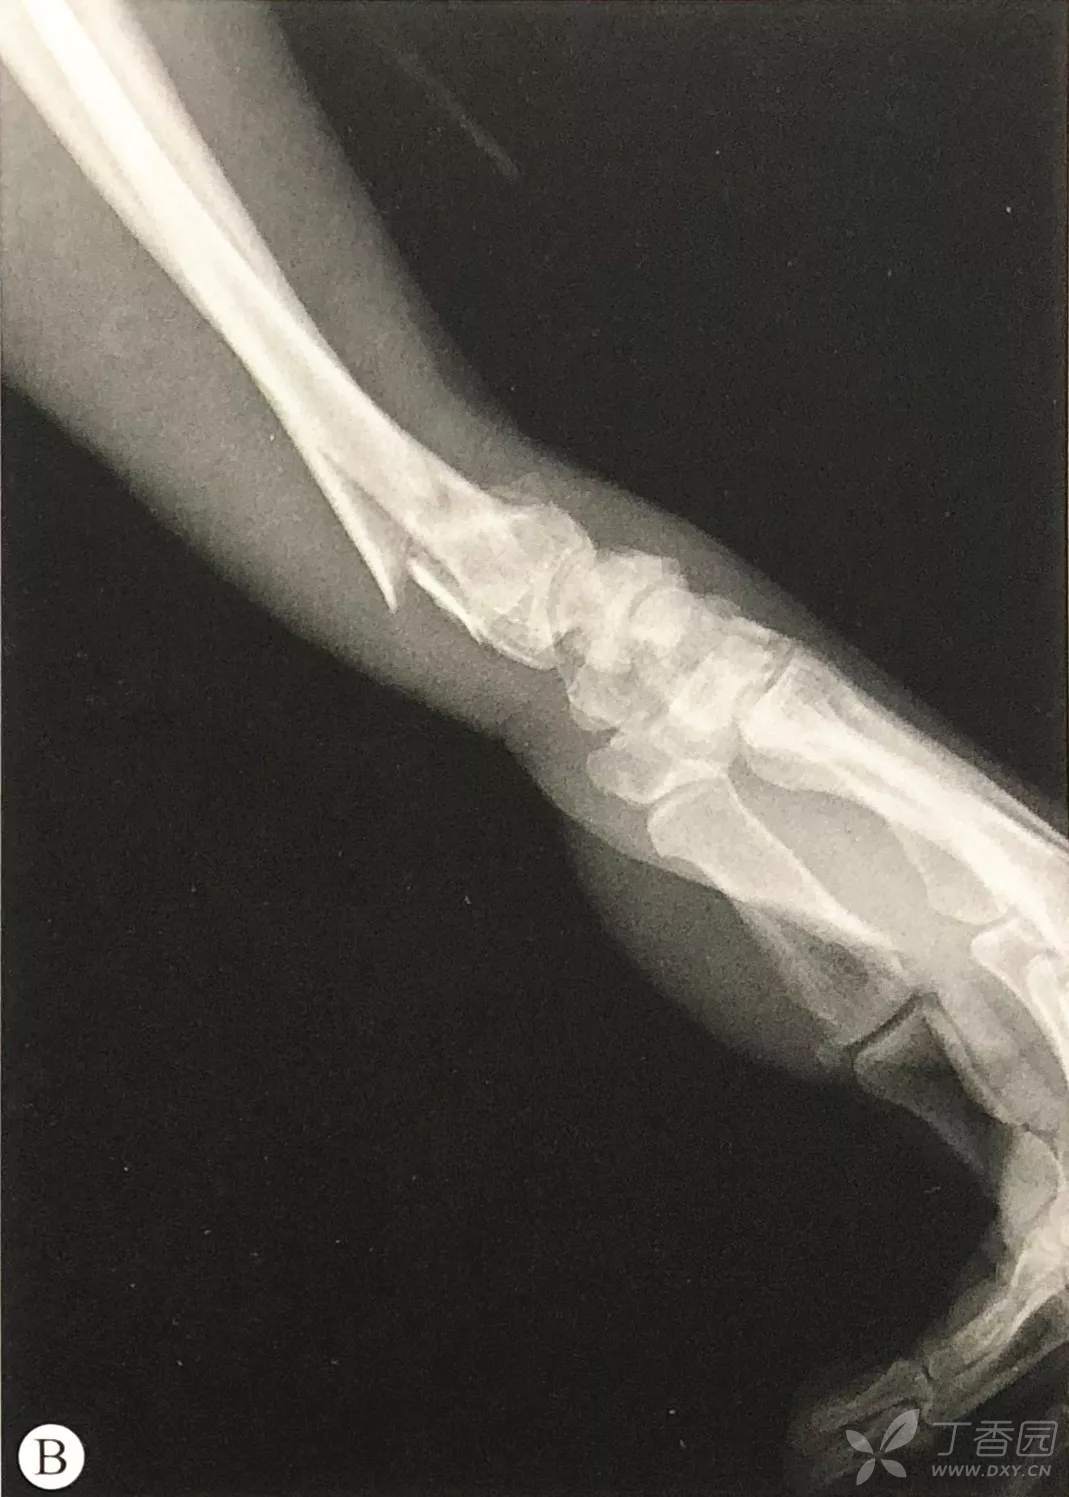

桡骨远端骨折手术技巧:切开复位内固定术

背向成角>15°者:

关节内骨折: